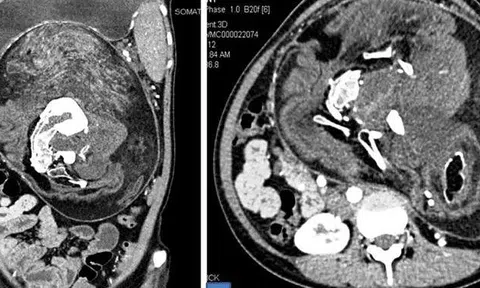

Mang song thai suốt 17 năm không hề hay biết

Bụng cô gái ở Ấn Độ cứ to dần dù không ăn nhiều. Bác sĩ nghi có khối u, kết quả chụp CT bất ngờ phát hiện bào thai đôi.